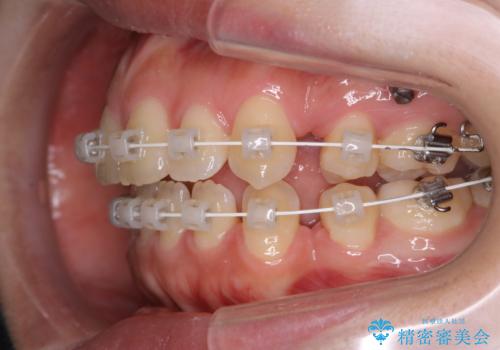

ワイヤー矯正中のクリーニング

- ワイヤー矯正中に、磨ききれないところがあるのと、口臭が気になるとのことでした。

そのためPMTC30分コースを行いました。

ワイヤー矯正中は、装置の周りに汚れが付きやすく虫歯や歯周病のリスクが高まります。そのため、ワイヤー調整の診察の際、一緒にクリーニングを行うことで、虫歯・歯周病・口臭予防になります。歯ブラシだけでは取り除くことが難しい細かい部分などに、専門的な機械や機材を使用して定期的なケアを行うことをおすすめしています。